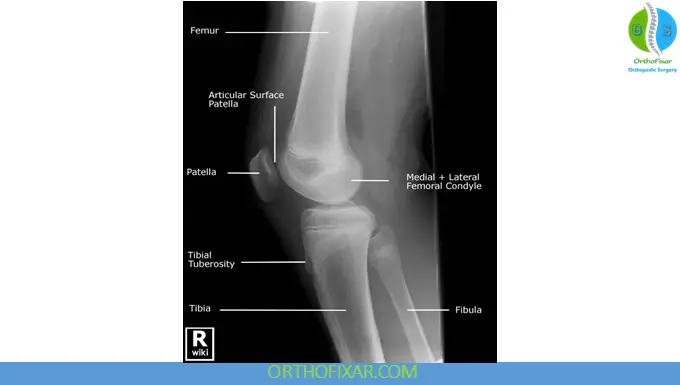

Lateral View

The lateral knee X-ray is typically obtained with the knee flexed to approximately 45°. This view is essential for evaluating:

- Patellar position and height (using patellar length–tendon ratios)

- Osgood–Schlatter disease

- Fabella (present in approximately 20% of the population)

- Avulsion fractures (arcuate sign, ACL or PCL insertions)

- Myositis ossificans

Standing lateral views are particularly useful in determining normal versus abnormal patellar tracking in a normal knee x ray.